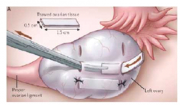

| 12:06, 12 במרץ 2015 | Cryonics3.png (קובץ) |  |

128 קילו־בייטים | Motyk | 1 | |

| 11:37, 12 במרץ 2015 | Cryonics2.png (קובץ) |  |

88 קילו־בייטים | Motyk | 1 | |

| 11:33, 12 במרץ 2015 | Cryonics1.png (קובץ) |  |

93 קילו־בייטים | Motyk | 1 | |